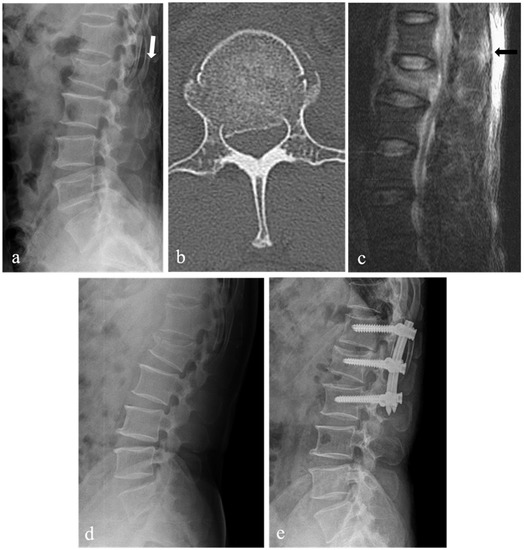

| Spinal canal compromise (%) ‡ | 27.9 ± 7.6 | 35.7 ± 13.3 | 0.03 |

| Loss of vertebral body height (%) ‡ | 28.6 ± 7.8 | 34.1 ± 6.0 | 0.01 |

| Kyphotic angle (°) ‡ | 10.1 ± 6.2 | 13.9 ± 5.0 | 0.04 |

| Spinal canal compromise | 1.26 | 1.00 to 1.42 | 0.04 |

| Loss of vertebral body height | 1.11 | 1.02 to 1.15 | 0.02 |

| Kyphotic angle | 1.33 | 1.01 to 1.47 | 0.04 |

| Spinal canal compromise | 1.316 | 1.01 to 1.41 | 0.03 |

| Kyphotic angle | 1.416 | 1.02 to 1.55 | 0.03 |